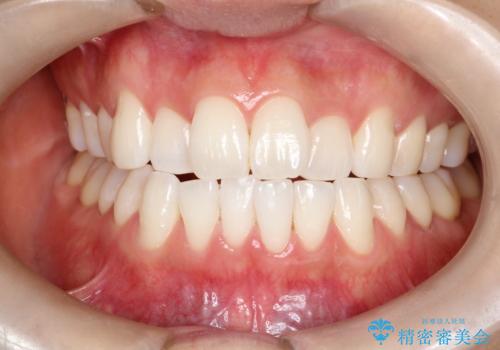

- 久しぶりの来院で歯磨きチェックとクリーニング希望とのことでした。染め出しとPMTC30分コースを行いました。

一見きれいに見える歯でも、染め出し(歯垢染色液)を使うとこのように歯と歯茎の境目や、歯と歯の間などに磨き残しがあることがわかります。歯磨きには、いつも気をつけているから磨き残しはナシと思っていても、実際完璧に磨ききることはなかなか難しいです。歯科医院にて、専門の機械で定期的なPMTCを行うことが大切です。